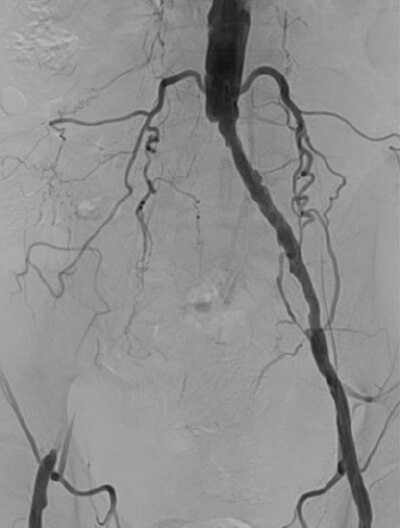

これらの血流が低下すると、歩行時の足の痛みや、足にできた傷が治らないなどの症状が出現します。これが下肢閉塞性動脈硬化症です。カテーテルを用いた実際の下肢動脈造影の映像がこのようになります(D)。

右腸骨動脈領域の閉塞 D

右腸骨動脈領域の閉塞

左浅大腿動脈の閉塞